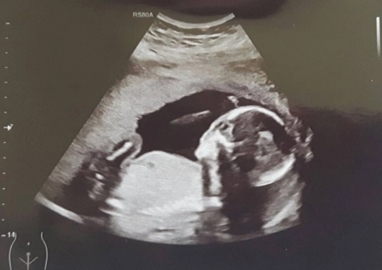

Emily Taylor, 31 tuổi, ở Brecon, Wales, Anh mắc hội chứng tử cung đôi khiến cô có hai ống dẫn trứng và hai cổ tử cung.